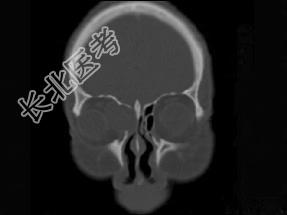

- 多项选择题女性38岁,右侧眼球运动障碍伴眼球突出4个多月, CT扫描如图,请选择正确的描述和答案 ( )

A、右侧筛窦内可见囊性肿块影,边缘光整

B、囊性肿块向右侧眼眶内突入,压迫内直肌

C、右侧眶内壁呈受压变薄、断裂

D、考虑为右侧筛窦黏液囊肿

E、考虑为筛窦癌